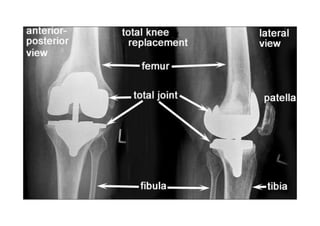

RADIOLOGIA DO

TRAUMA DO ESQUELETO

Referência: http://www.accessexcellence.org/RC/VL/